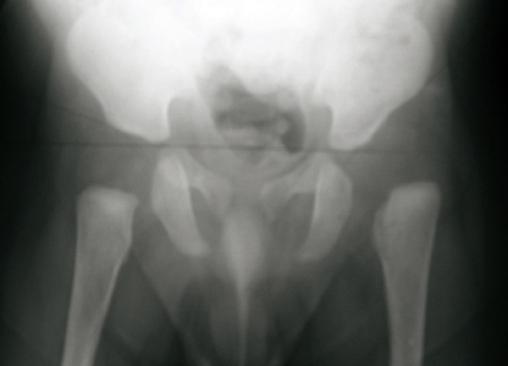

Radiographie du bassin de face chez un nourrisson ayant une luxation congénitale de la hanche gauche.